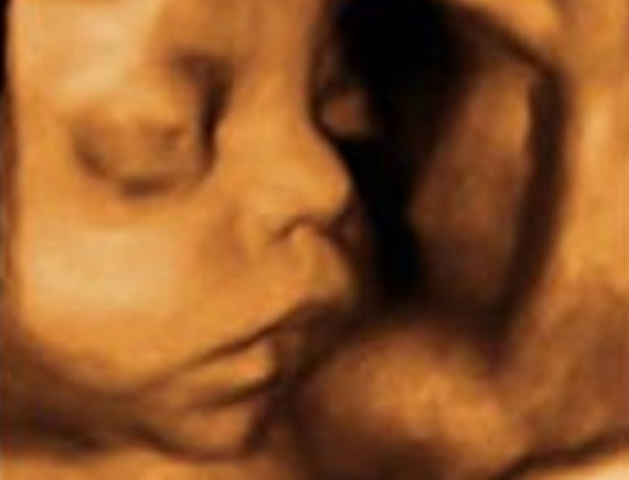

• Vigésima quinta semana.

Vigésima quinta semana.

El bebé pesa ya 700 gramos y mide 22 centímetros desde la cabeza al final de la columna.

Los párpados del niño se abren y se pueden ver los ojos. La lengua sale de la boca y se mueve hacia los lados, sonríe y empieza a hacer gestos.